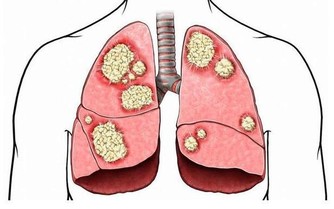

2.癌症

癌症也是這一年齡段高發的疾病,如肝癌、肺癌、乳腺癌、胃癌等。

腫塊

癌細胞惡性增殖所形成的,有些可用手在體表或深部觸摸到。甲狀腺、腮腺或乳腺的癌可在皮下較淺部位觸摸到。

疼痛

腫瘤的膨脹性生長或破潰、感染等使末梢神經或神經乾受刺激或壓迫,可出現局部疼痛。

出血

癌組織侵犯血管或癌組織小血管破裂而產生。如肺癌患者可能咯血或痰中帶血;胃癌、食管癌、結腸癌則可能嘔血或便血,子宮頸癌可能有陰道流血。